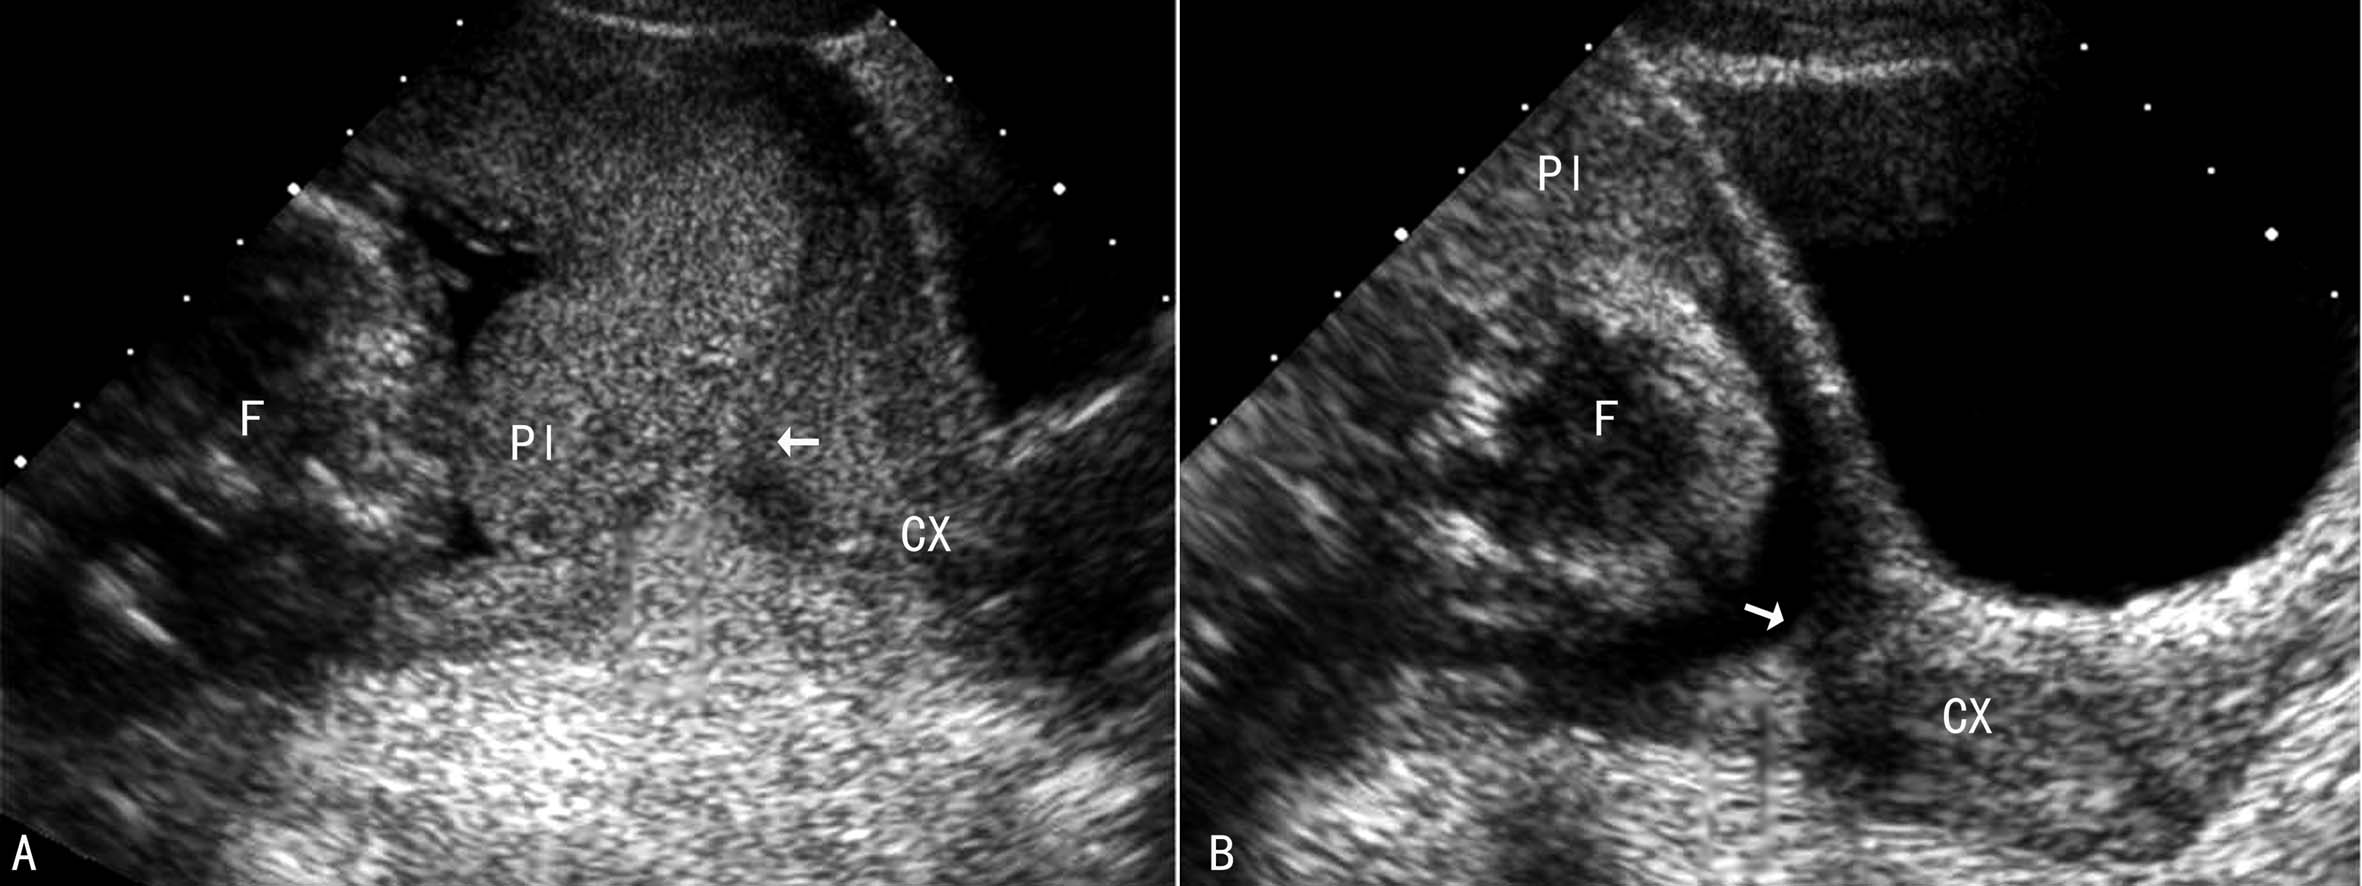

子宫下段局限性收缩引起子宫壁局部增厚可形成类似PLP的声像图或将位于正常位置的胎盘压向宫颈形成类似PLP声像图。30~60min复查可容易地将这种现象与PLP区分开来(图5)。

图5子宫局部收缩形成类似前置胎盘的声像图